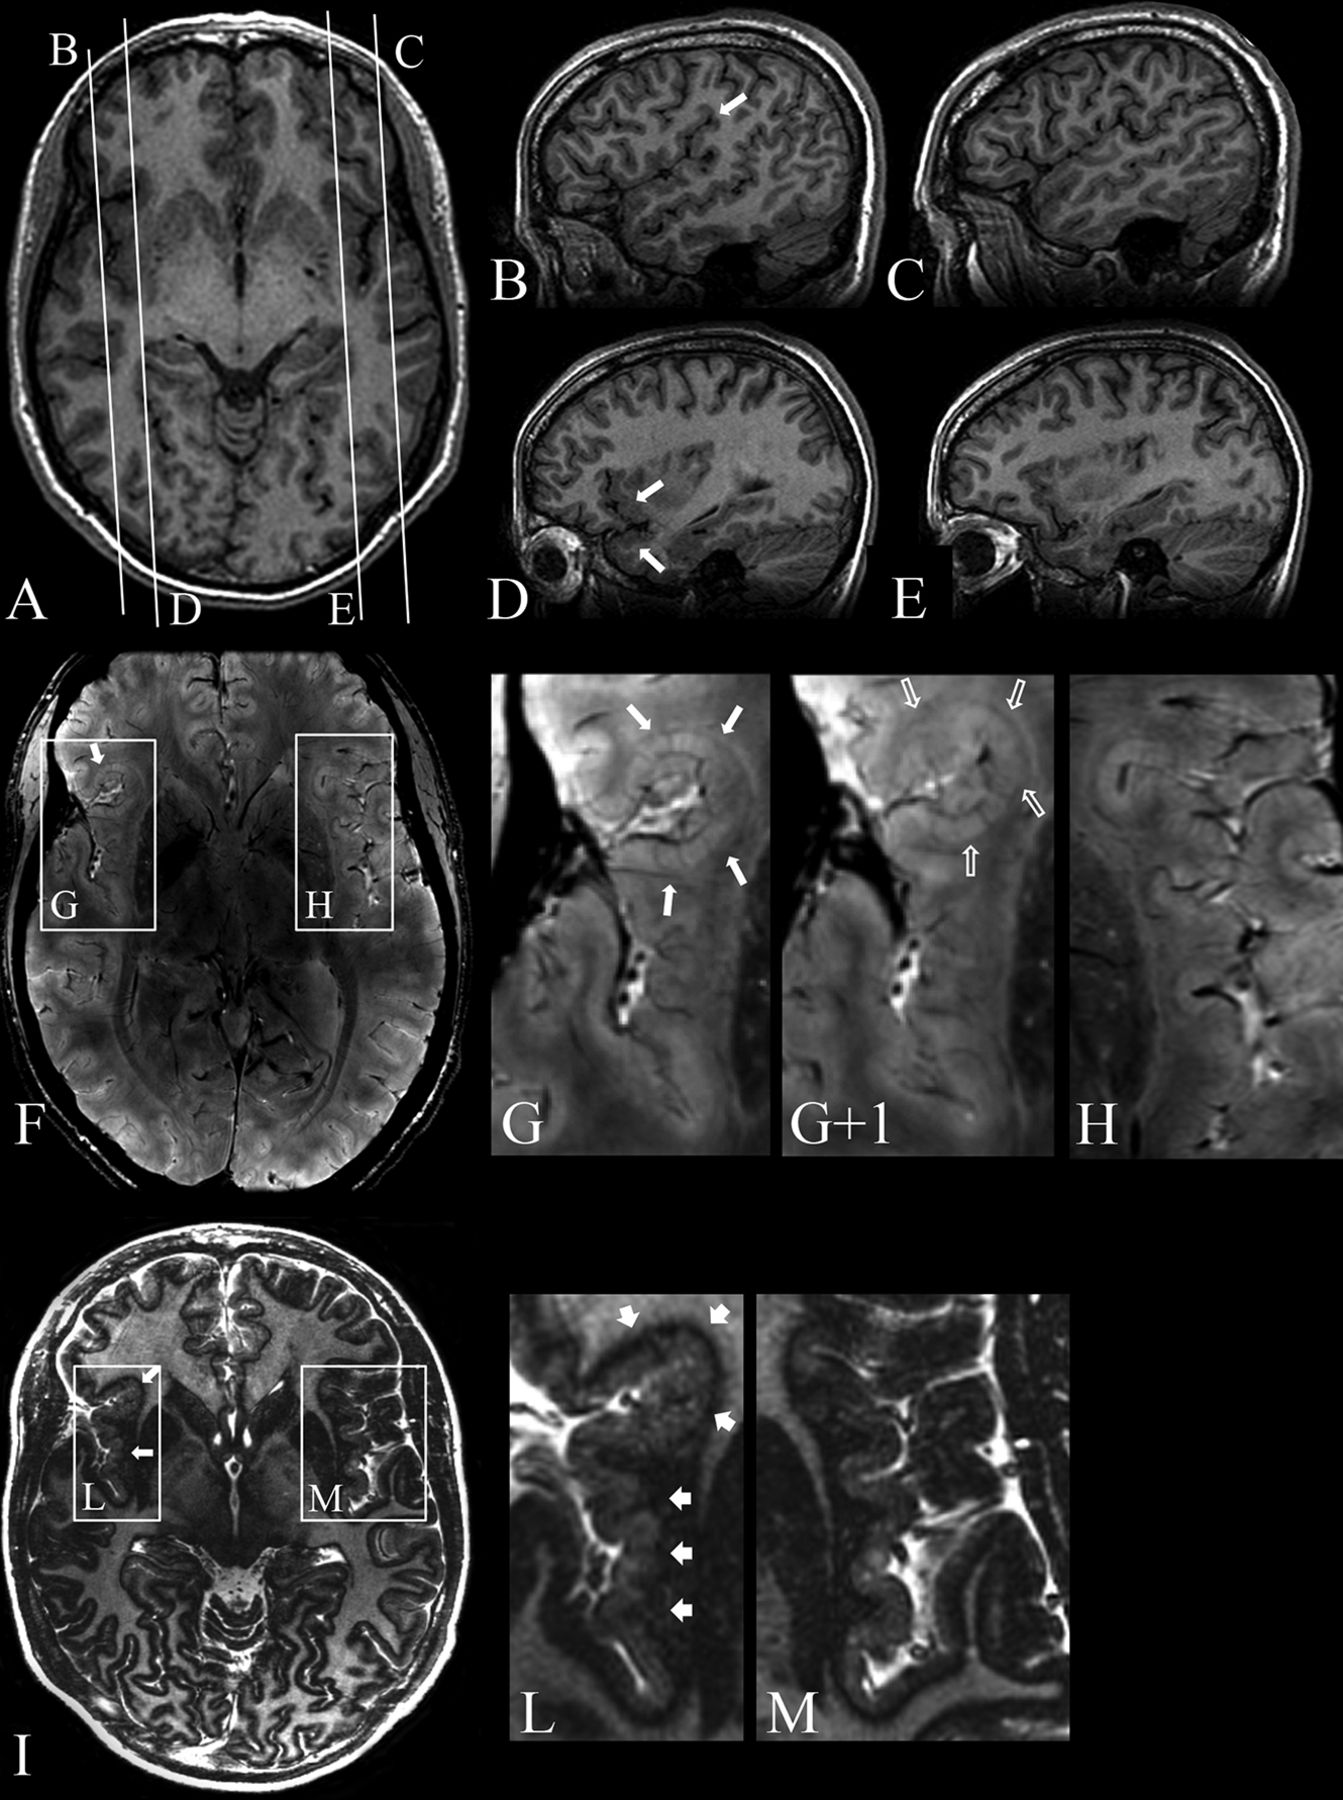

In all patients, SWAN imaging revealed numerous dilated superficial veins draining the deeper infoldings of polymicrogyria, which were not visible at 3T by using conventional (FSPGR, FSE, and IR) sequences. These large venous structures, which have been described previously,39 appeared to be roughly proportional to the depth/size of the cortical infolding and extent of polymicrogyria (Fig 3).

Patient 9. 7T axial 3D SWAN (A, magnified in B) and its minimum intensity projection reconstruction (C). A, Bilateral polymicrogyria involving the left frontal operculum and Sylvian fissure and the right Sylvian fissure and temporal lobe. B, Details of the polymicrogyric cortex in the right temporal lobe (magnified). C, Minimum intensity projection reconstruction shows dilated superficial veins in correspondence with the polymicrogyric areas (arrowheads); the large vascular structures running through the polymicrogyric sulci (arrows) define the location and the extent of the malformation.

In addition to producing more accurate morphologic details of the polymicrogyric cortex, SWAN imaging at 7T detected deoxygenated venous blood that allowed visualization of the superficial and deep cerebral veins. Although 3T SWAN can also visualize venous abnormalities, there is no previous report emphasizing this finding at 3T, to our knowledge. At 7T, the polymicrogyric cortex was shown to harbor numerous dilated superficial veins, whose representation seemed to be roughly proportional to the extent and severity of the cortical malformation. The pial veins were visible as linear hypointensities, orthogonal to and penetrating into the cortex. Following the expected course of the sulci, the pial veins defined the complexity of cortical gyration, revealing the contour of polymicrogyria. SWAN–minimum intensity projection images, which enhance the visualization of veins while attenuating the signal from brain tissue, revealed large vascular structures running through the sulci, draining from the polymicrogyric cortex into the pial veins. These findings reinforce previous imaging observations indicating anomalous venous drainage in dysplastic cortical areas.39,45 On the other hand, although perfusion failure is a recognized cause of polymicrogyria, there is no reported neuropathologic evidence of vascular malformations associated with it.6,46⇓⇓–49